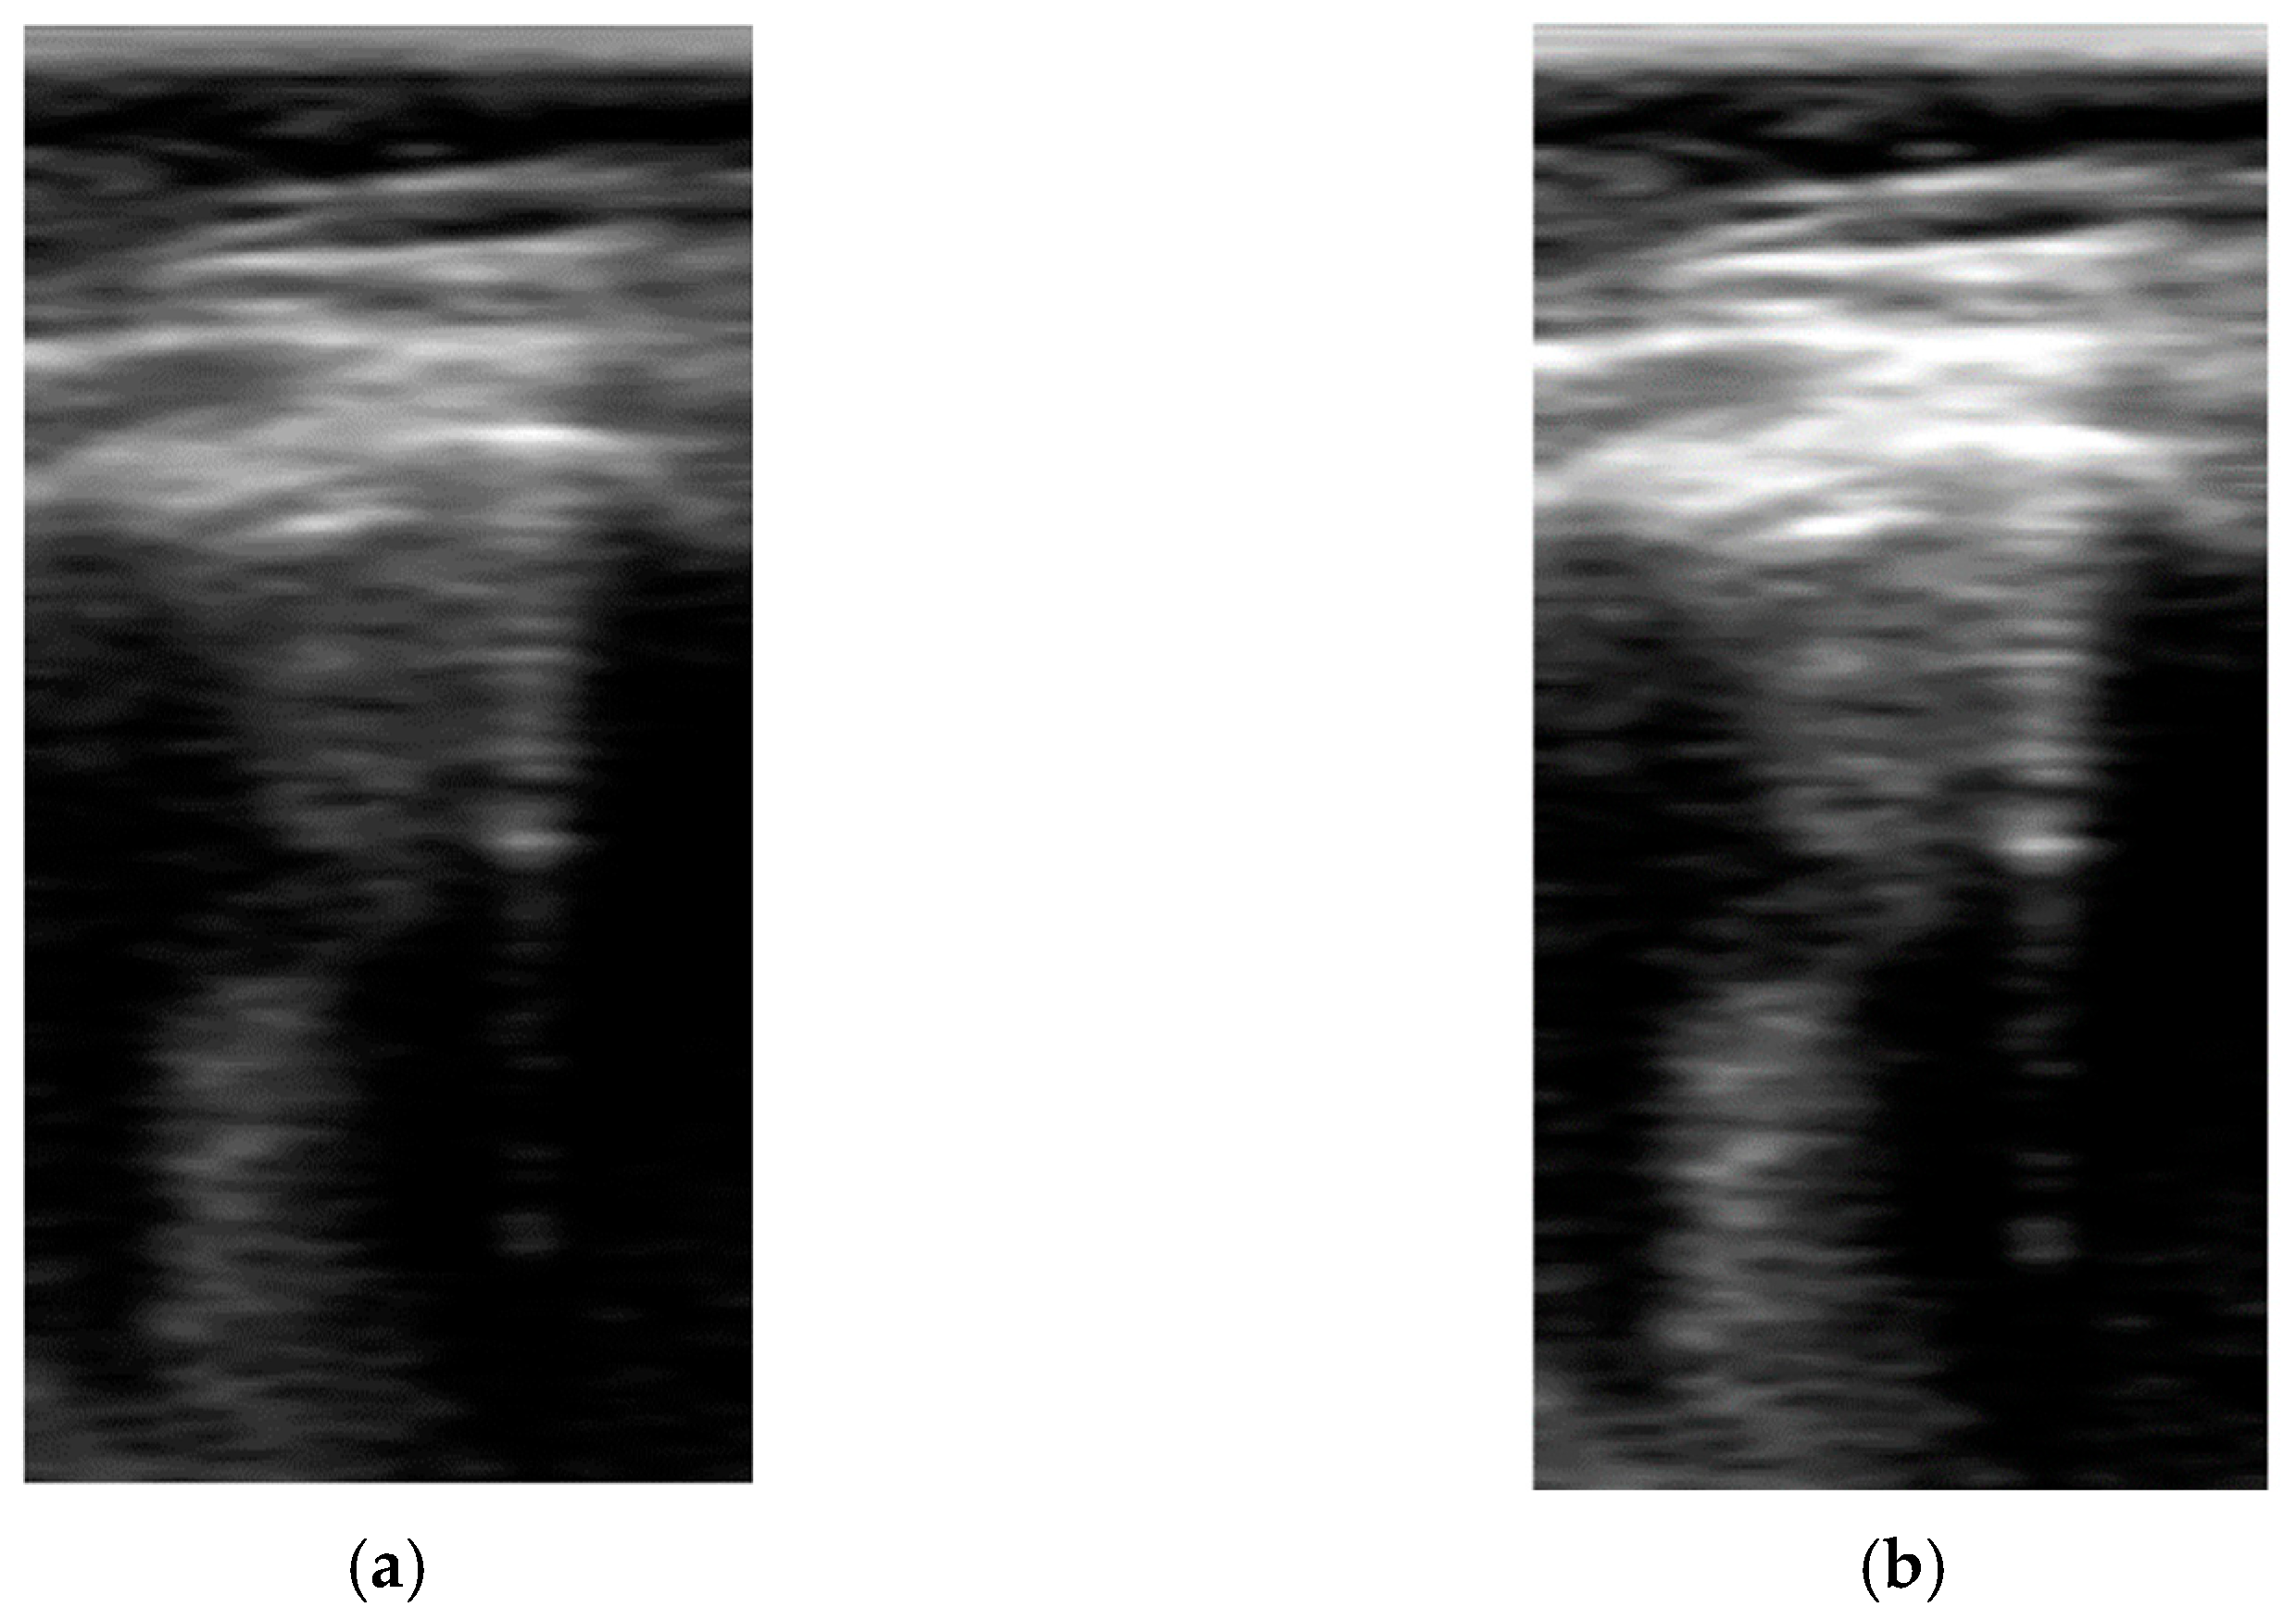

Figure 3.

Comparison between sectorial image (a) and B-Scan (b).

The size of the vertical direction is related to the frequency content of the signal and the sampling rate. For an ideal 100% bandwidth array, the maximum frequency content of the signal envelope is equal to half the array center frequency. To reconstruct the envelope without aliasing, the pixel density in the vertical direction should be, at least, able to sample the signal at double of that frequency (Nyquist criteria). For the array used in this work with 3.5 MHz center frequency and 70% bandwidth, the number of pixels required for sampling up to 70 mm and 90 mm is 210 and 294, respectively. Based on these numbers, a height of 256 was selected for the network, which imposes a trade-off between training and inference cost and image quality. In cases when larger images are used, they should be scaled down using compression algorithms that preserve the artifacts’ information. For example, in the scanner used in this work, a data reduction algorithm without peak information losses is available [26] and was used to accommodate the B-Scan height to the network size. In Figure 3, a comparison example between sectorial and B-scan images is shown.